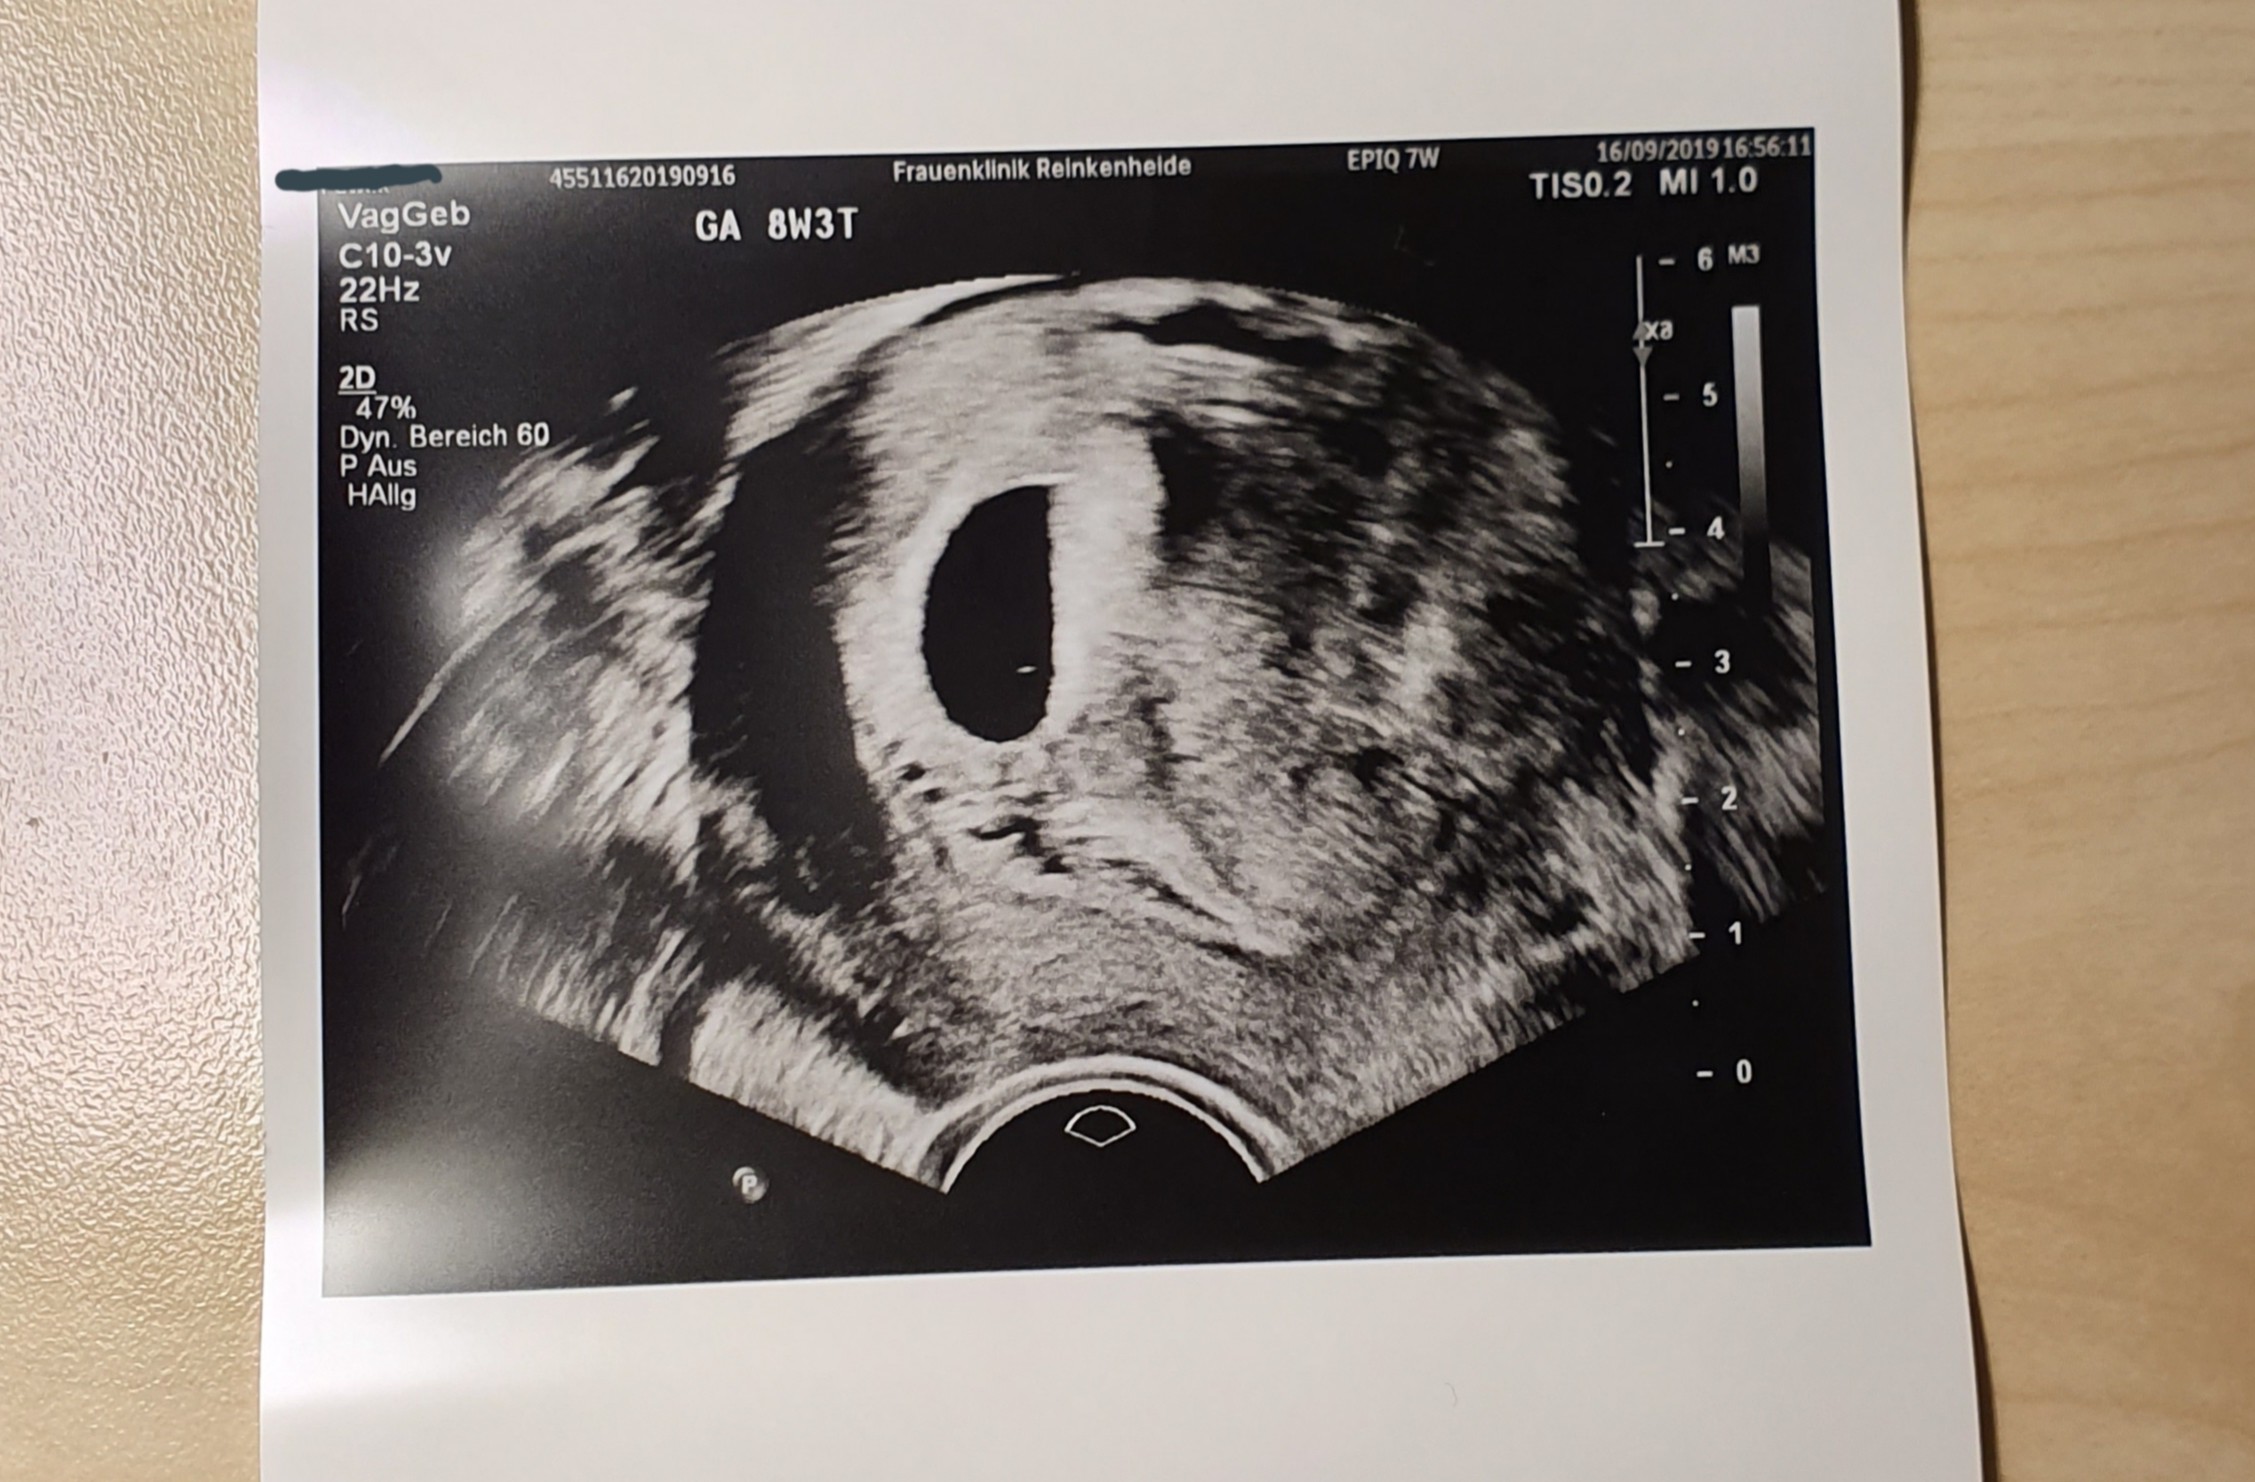

U mnie dużo się dzieje lekarz narobił mi nadziei bo 9.09 znalazł w końcu pęcherzyk żółtkowy następna wizyta miała być 23.09 ale w piątek 13.09 pobolewal mnie brzuch i miałam jakieś dziwne kłucia w szyjce macicy tak jak by co jakiś czas ktoś wbijał mi igłe nie mam daleko do lekarza więc zadzwoniłam opisałam sytuację więc lekarz kazał przyjść zrobil USG i stwierdzil ze cos tam kest ale jest to bardzo małe kontrola w poniedziałek 16.09 I tego dnia dostałam skierowanie do szpitala na łyżeczkowanie macicy popołudniu wybrałam się do szpitala pobrali mi krew lekarz mnie zbadał zrobil USG i niestety potwierdził to co powiedział mój lekarz ! Wynik hcg 22861 powinnam zostać w szpitalu do dzisiaj i czekać na nastepne badanie krwi ale postanowilam wrocic do domu i dzis jade na kontrole na 15 bede miala kolejne badanie krwi jesli beta będzie rosła to zostaje na obserwacji bo pęcherzyk ciążowy rośnie Ale w środku jest tylko kropka wielkości lebka szpilki niżej wstawię zdjęcia! A jeśli beta będzie spadać to albo będę musiała czekać na poronienie samoistne albo łyżeczkowanie więcej będę wiedziała dzisiaj myślę że około 17 .

Pierwsze zdjęcie jest od mojego lekarza z 9.09

Drugie ze szpitala 16.09

U mnie wczoraj pokazał się zarodek, serce bije mocno :) pomimo mniejszych przyrostów beta hcg wszystko jest w porządku.